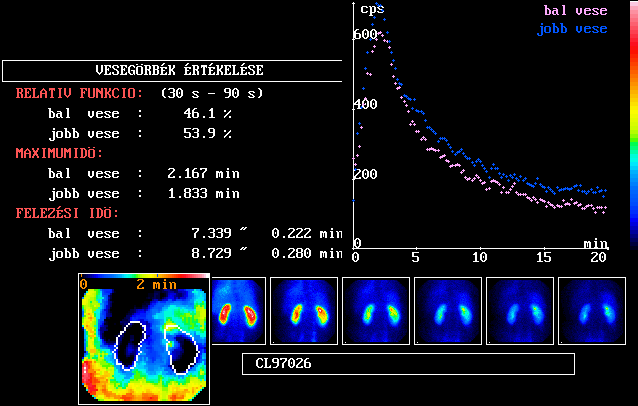

Normális dinamikus veseszcintigáfiás

vizsgálat

[Tc-99m] MAG3-mal végzett vizsgálat összefoglaló

eredménylapja. Részei:

- A jobb felső részen a vesék idő-aktivitás

görbéje látható, a háttér

levonása után.

- A bal felső részen az aktivitás-görbékből

számolt paraméterek.

- A relatív funkciót

a felszálló szakaszban mért radiofarmakon-aránnyal

jellemezzük. Az 50-50%-tól 5-6 % eltérés

még normálisnak tekinthető. A különbség

oka lehet, ha a vesék eltérő mélységben

helyezkednek el, ekkor ugyanis a beteg testében elnyelődő

sugárzás a két oldalon más-más.

- A maximum időpontja MAG3-mal

3-4 perc alatt normális.

- A kiürülési felezési

időt a leszálló szárra illesztett

exponenciális görbéből számoljuk.

Értéke MAG3 esetén 12-15 perc alatt normális.

- A jobb alsó részen a vizsgálat 6 részösszeg-képe

látható. A radiofarmakon kezdetben egyenletesen

az egész parenchymában jelenik meg, majd a kéregből

távozva az üregrendszerben tovább megmaradhat.

Normális esetben az üregrendszer alig vagy egyáltalán

nem különül el a vese többi részétől.

- A bal alsó részen az áthaladási

idő parametrikus kép a vese körvonalán

belül normális esetben nem vagy alig mutat olyan területet,

amelynek radiofarmakon-transzportja elhúzódó.

További hasznos kvantitatív információ

nyerhető a radiofarmakon-transzportról a dekonvolúció-analízis alkalmazásával.